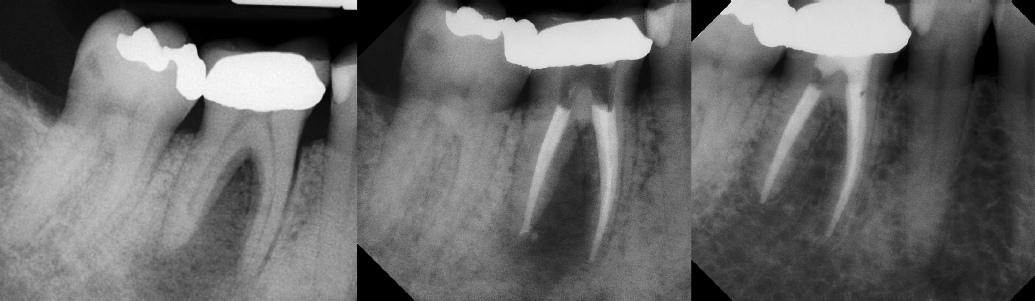

Pre-op Post-op 6 mos.